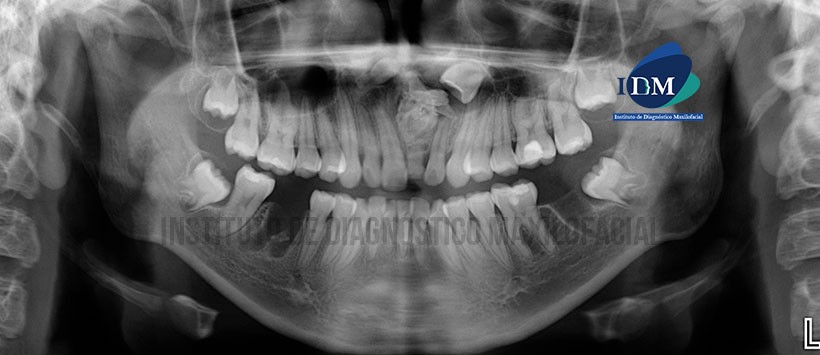

Paciente de sexo masculino de 15 años de edad acude al Instituto de Diagnóstico por Imágenes para evaluación imagenológica debido a la ausencia clínica de la pieza 21.

A la evaluación de la radiografía panorámica se aprecia las terceras molares en evolución intraosea, ausencia de piezas 36 y 46 con presencia de sus lechos alveolares en proceso de cicatrización, múltiples restauraciones y persistencia de la pieza 61. Sin embargo lo mas resaltante es la presencia de un odontoma compuesto de gran tamaño localizado en la zona anterosuperior, condicionando la correcta erupción e la pieza 21 y también se evidencio la presencia de una pieza supernumeraria en posición invertida próxima al odontoma. (Figura 1)